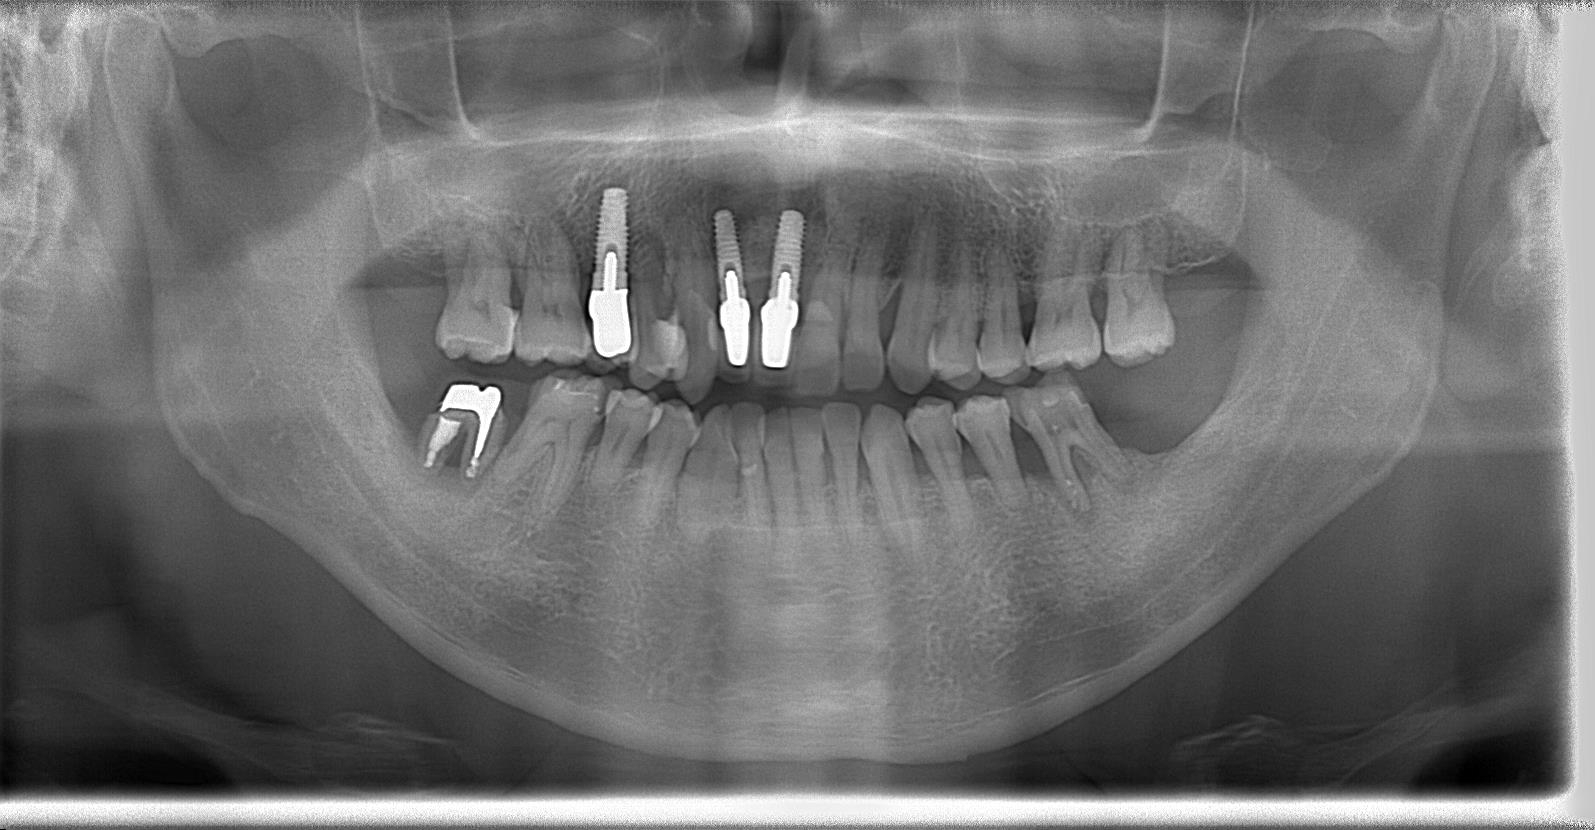

50代男性、インプラント症例です。

術後パノラマレントゲン写真

インプラント埋入した状態は良好です。